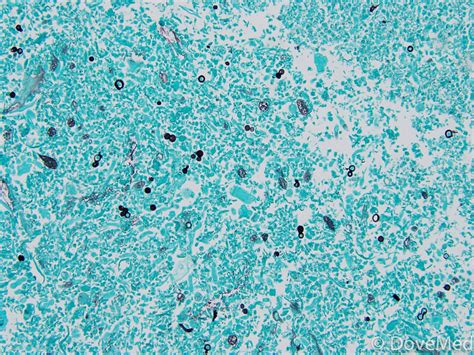

Blastomycosis is a pulmonary disease caused by inhaling spores of the dimorphic fungus Blastomyces dermatitidis. Occasionally, the fungi spread hematogenously, causing extrapulmonary disease. Symptoms result from pneumonia or from dissemination to multiple organs, most commonly the skin.

Blastomycosis is a type of fungal infection that occurs when a person inhales spores of the Blastomyces dermatitidis or Blastomyces gilchristii fungus. As the fungus tends to live in moist soil and decomposing leaves or wood, a person is most likely to inhale the spores when performing an activity that disrupts the soil, such as:

Infection most typically occurs following disturbance of soil in areas inhabited by Blastomyces; disturbance releases fungal spores into the air, resulting in their inhalation. Most cases of blastomycosis in humans involve Blastomyces dermatitidis. Infection generally is mild, and some persons are asymptomatic.